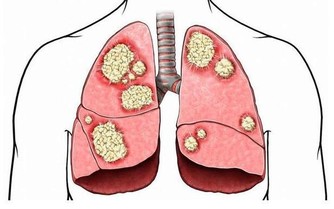

5、拇指揉鼻 一分鐘

雙手拇指上下揉鼻50次,可祛風雍塞,開肺竅,對感冒、上呼吸道感染、支氣管炎,甚至對心臟病、動脈硬化症都有防治功效。